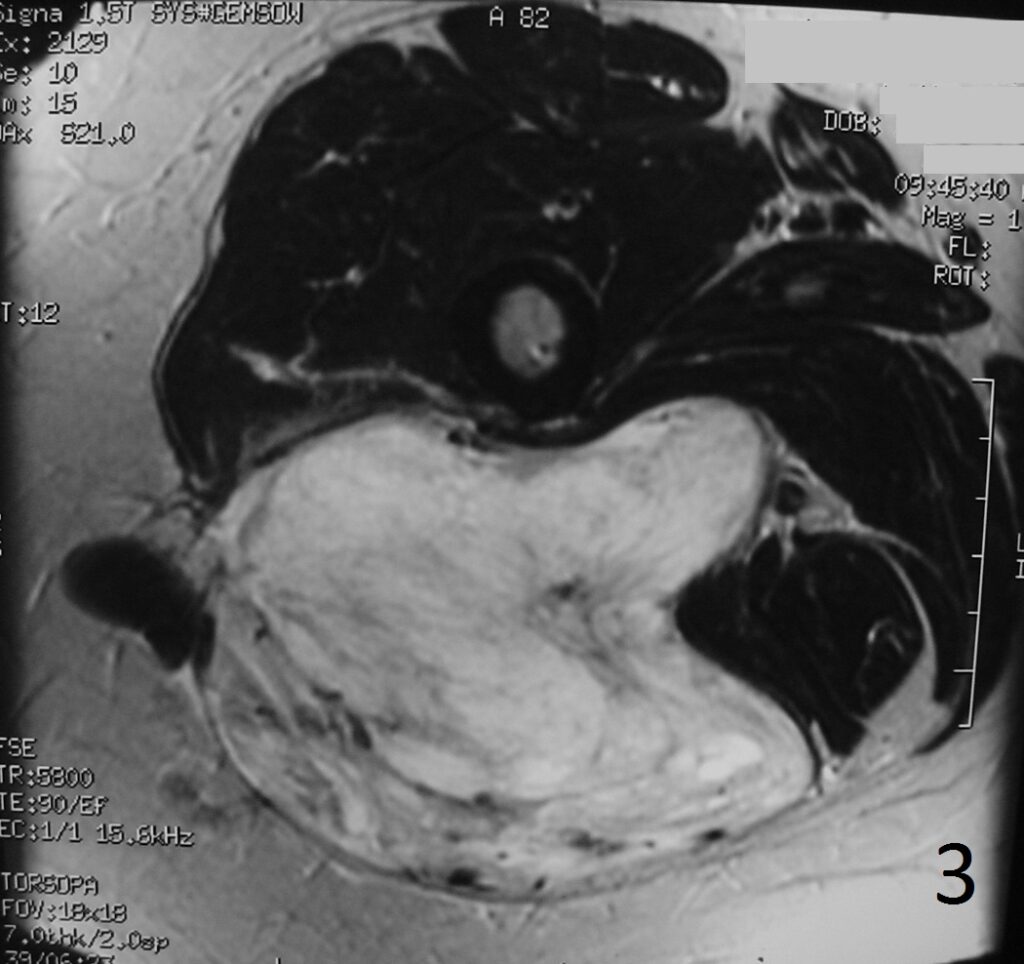

Fig 4-6: T2W FS demonstrates same features (Fig. 4) . Sagittal T1W (Fig. 5) and T1W FS (Fig. 6) of same case.